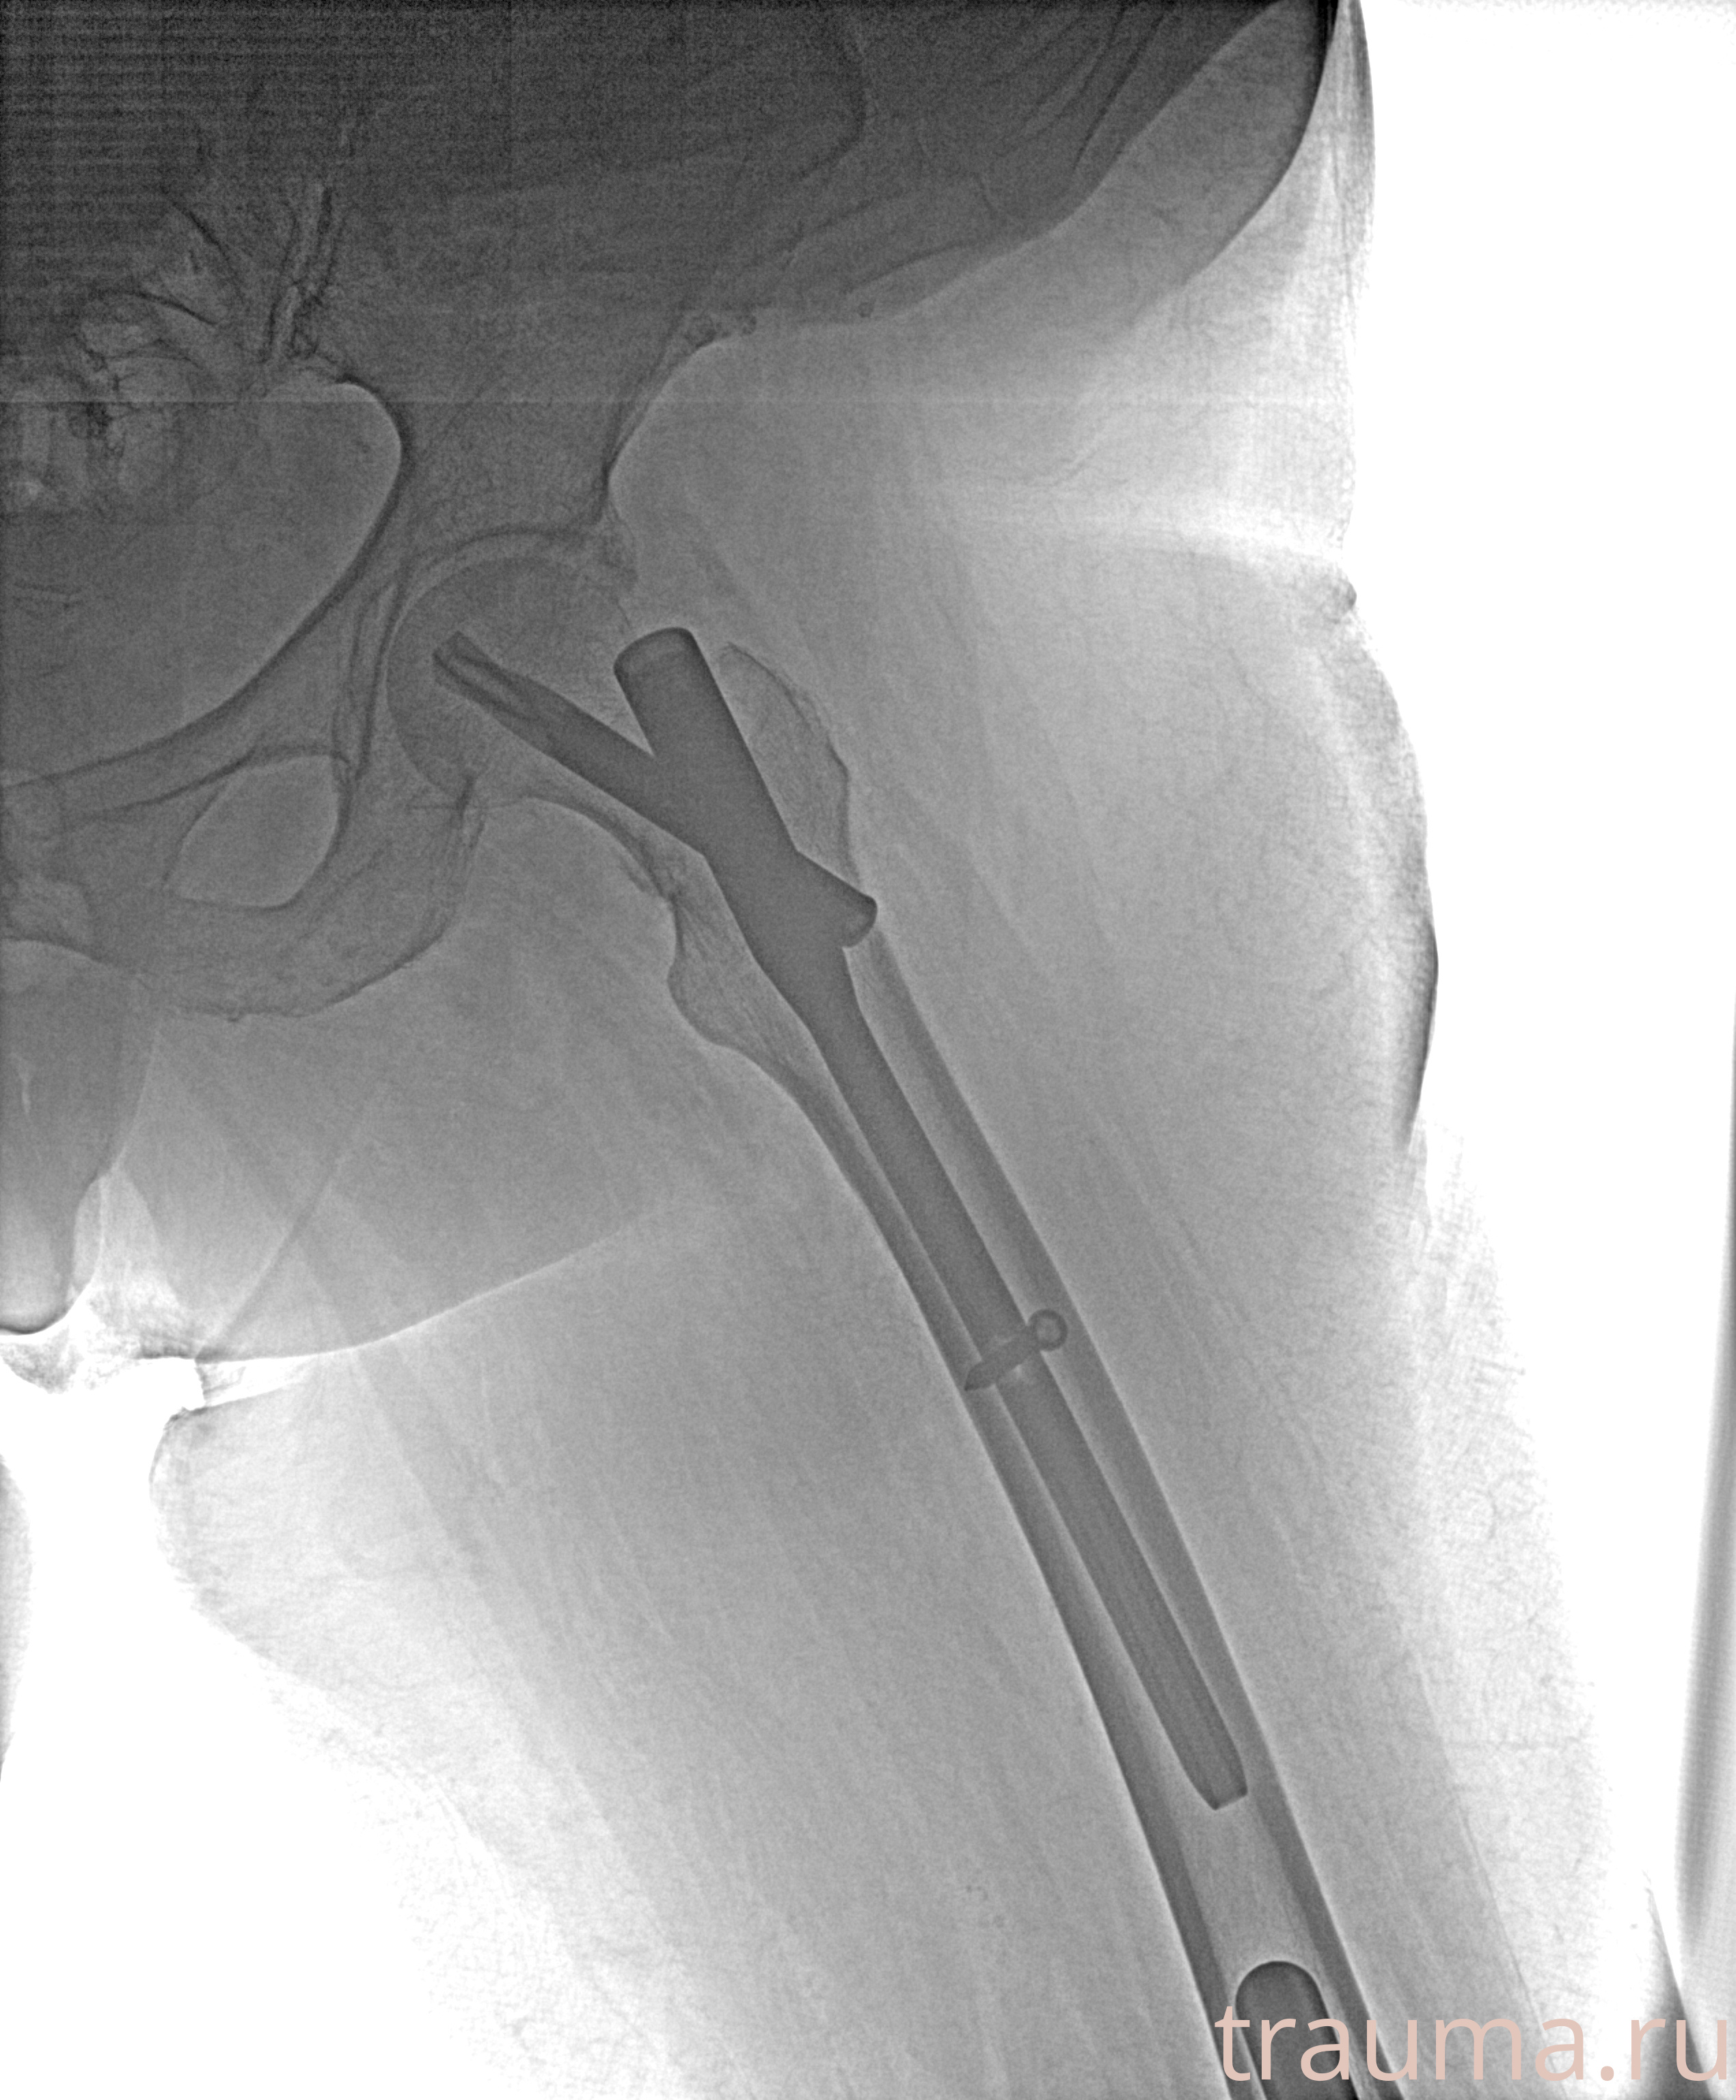

Рентгенограммы

Рентген на дому: по вашему адресу приезжает врач-рентгенолог, травматолог-ортопед с мобильным рентгеновским аппаратом, проводит диагностику травмы или заболевания, делает необходимые рентгенограммы, дает рекомендации по дальнейшему лечению. Получить качественные снимки в домашних условиях возможно благодаря уникальной методике, разработанной МосРентген Центром для института  Склифосовского